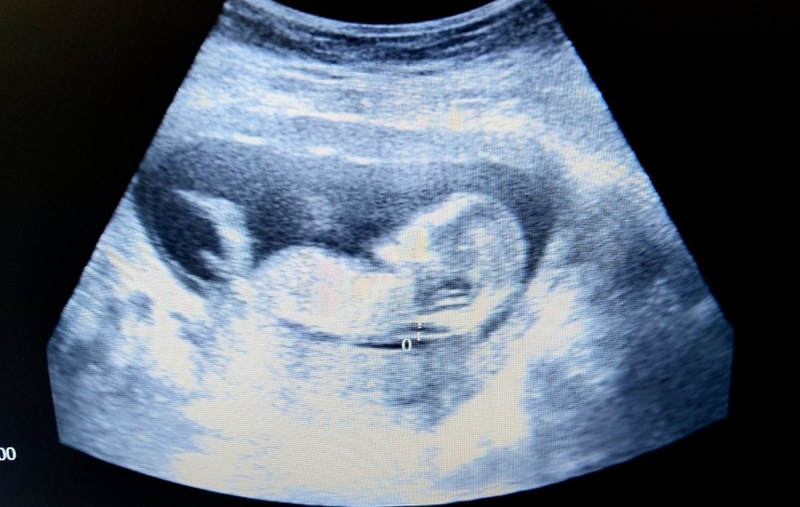

Tư vấn sức khỏe sinh sản: Độ mờ da gáy 1.6 mm có bình thường không? 1

Siêu âm đo độ mờ da gáy là một xét nghiệm sàng lọc quan trọng